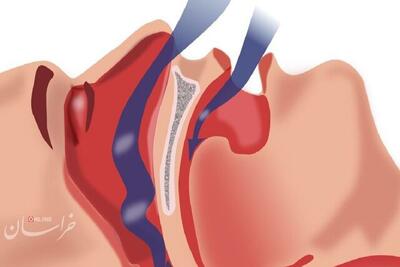

کمبود خواب مانع کاهش وزن

خراسان رضوی بیش از یکسوم بزرگسالان در ایالات متحده و بریتانیا به دلایل مرتبط با زندگی مدرن مانند استرس، محو شدن مرزهای کار و زندگی یا استفاده بیش از حد از وسایل الکترونیکی به طور منظم خواب کافی ندارند. البته نتایج مطالعات قبلی نیز نشان داده اختلالات خواب میتواند باعث بروز انواع مشکلات سلامتی از جمله …